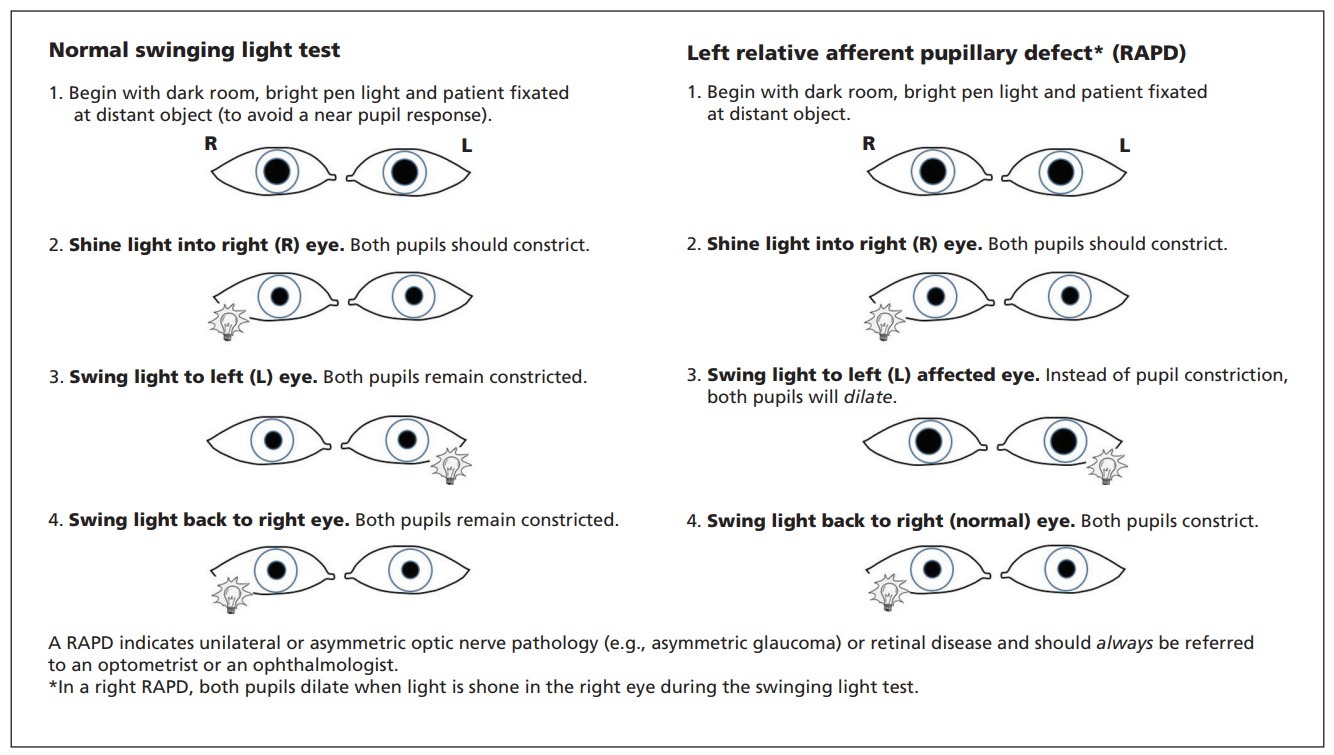

- Afferent pupillary defect

Afferent pupillary defect

Due to prior optic neuritis.

An afferent pupillary defect may be present even in patients who have not had a clear clinical episode of optic neuritis